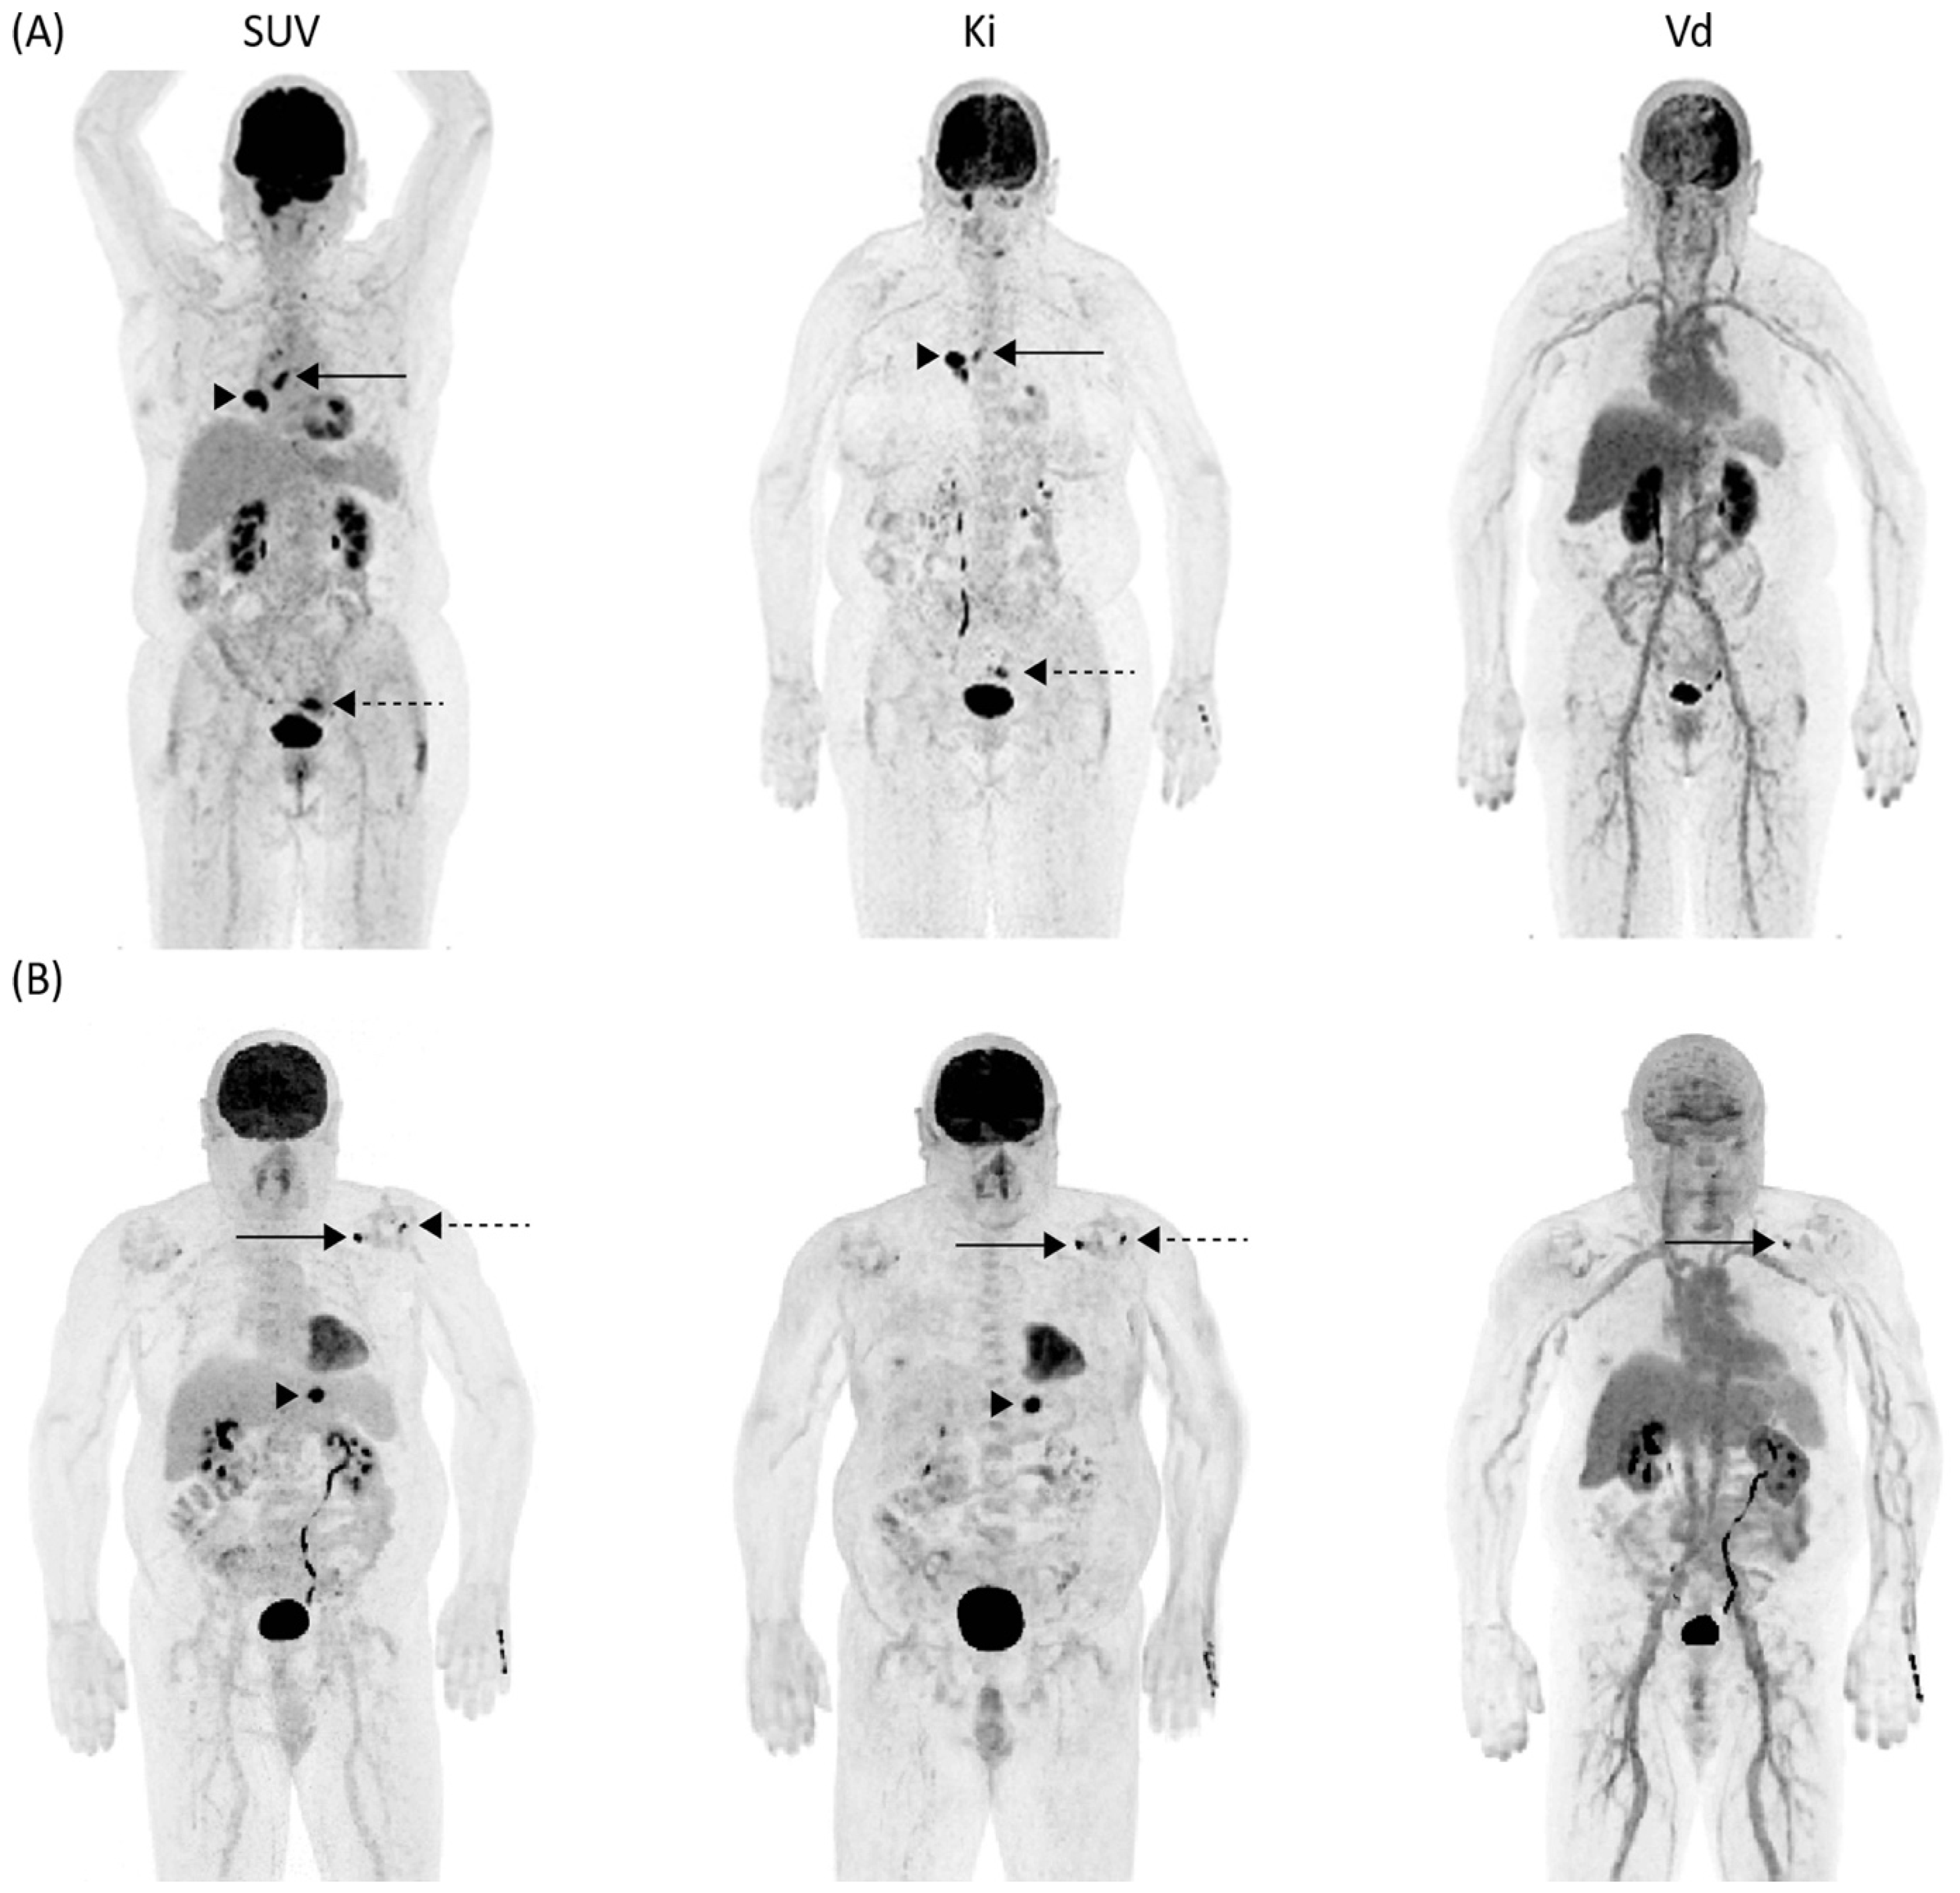

3.4. Differentiation of Malignant vs. Inflammatory Lesion in Clinical and Dynamic Imaging

4. Discussion